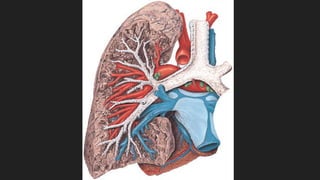

PULMONES

 Son órganos pares en los que se realiza la hematosis

 FORMA: Semicónica

- Vértice, sobresale por el orificio superior del tórax y ocupa la base del cuello.

- Base, es cóncava y semilunar, se apoya en el diafragma. La base derecha es algo más

elevada que la base izquierda.

- Cara medial, se encuentra el Hilio Pulmonar.

- Cisuras, son hendiduras que separan porciones del pulmón de forma parcial. Ambos

pulmones presentan una cisura oblícua y del derecho presenta una cisura horizontal.

Dividen al pulmón en lóbulos. El pulmón derecho presenta 3 lóbulos y el izquierdo 2.

ARBORIZACIÓN BRONQUIAL

Cuando penetran los bronquios principales al pulmón se dividen sucesivamente como las ramas

de un árbol.

Bronquios Secundarios o Lobares

Bronquios Terciarios o Segmentarios

Bronquiolos carecen de cartílagos y de glándulas.

LOBULILLO PULMONAR

Una de las últimas generaciones de los Bronquiolos es el Bronquiolo Lobulillar que ventila un

territorio pulmonar que es el Lobulillo Pulmonar. Cada bronquio Lobulillar se sigue dividiendo y

termina en los Bronquiolos Terminales que ventila un territorio pulmonar Acino Respiratorio

que consta de Bronquiolos respiratorios, conductos alveolares, sacos alveolares y

alveolos

PLEURA

Es una membrana serosa que envuelve a los

pulmones y le permite su desplazamiento. La pleura

derecha e izquierda son independientes.

Está formada por 2 hojas Parietal y Visceral entre las

que delimita una cavidad virtual que contiene una

pequeña cantidad de líquido.